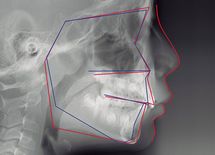

歯列矯正